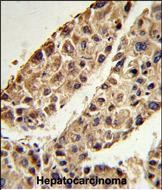

- Formalin-fixed and paraffin-embedded human hepatocarcinoma reacted with ITIH2 Antibody (C-term), which was peroxidase-conjugated to the secondary antibody, followed by DAB staining. This data demonstrates the use of this antibody for immunohistochemistry; clinical relevance has not been evaluated.